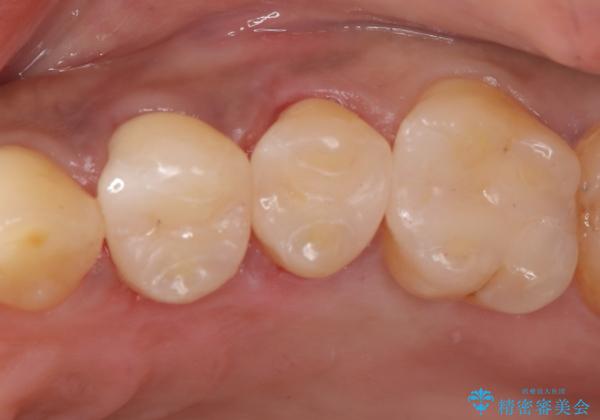

【セラミックインレー】虫歯になった詰め物部分を修復

- 前医で治療された詰め物の部分に、定期検診で虫歯が見つかったため、セラミックインレーにて修復治療を行いました。

接着時にはラバーダム防湿を行っています。